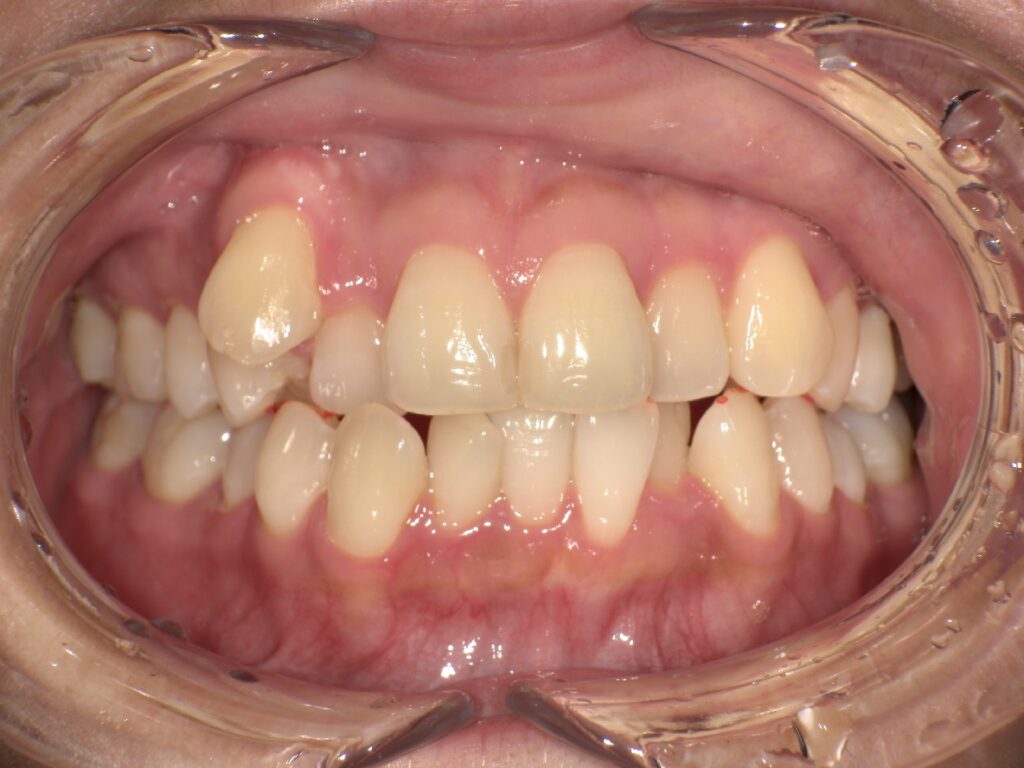

下記のケースでは、奥歯の噛み合わせが悪くなかったことから、患者様の希望もあり、部分矯正で対応いたしました。

上顎の前歯が大きく突出しています

明らかに前歯の突出感が改善し、患者様はこの時点でとても喜ばれていました

矯正治療終了時 部分矯正ということもあり、短期間で矯正治療を終了することができました